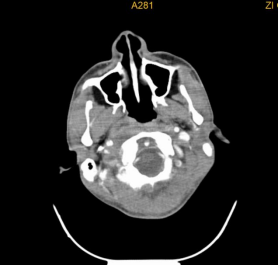

鼻咽癌颈淋巴结转移

鼻咽癌发生颈淋巴结转移的概率最高,约占60%,很多患者以颈部肿块为首发症状,鼻咽癌的颈部淋巴结转移位置常常在颈深上淋巴结(大概说就是我们耳垂下方区域)。